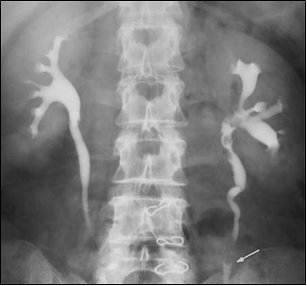

50세 남자가 식은땀을 흘리며 구토와 욕지기(nausea), 넓적다리 앞부분에서 음낭(scrotum)까지 이어지는 부위의 극심한 간헐통(intermittent pain)으로 병원에 왔다. 요관깔때기조영술(ureteropyelography) 사진이다. 통증과 관련된 신경은?

음부넙다리신경(genitofemoral nerve)은 L1-L2 신경근에서 유래하며, 복부와 골반의 다양한 구조물을 지배한다.

• 생식가지(genital branch)는 음낭(scrotum) 또는 대음순(labia majora) 등의 생식기 부위를 지배하고, 넙다리가지(femoral branch)는 넓적다리 앞부분의 피부를 지배한다.